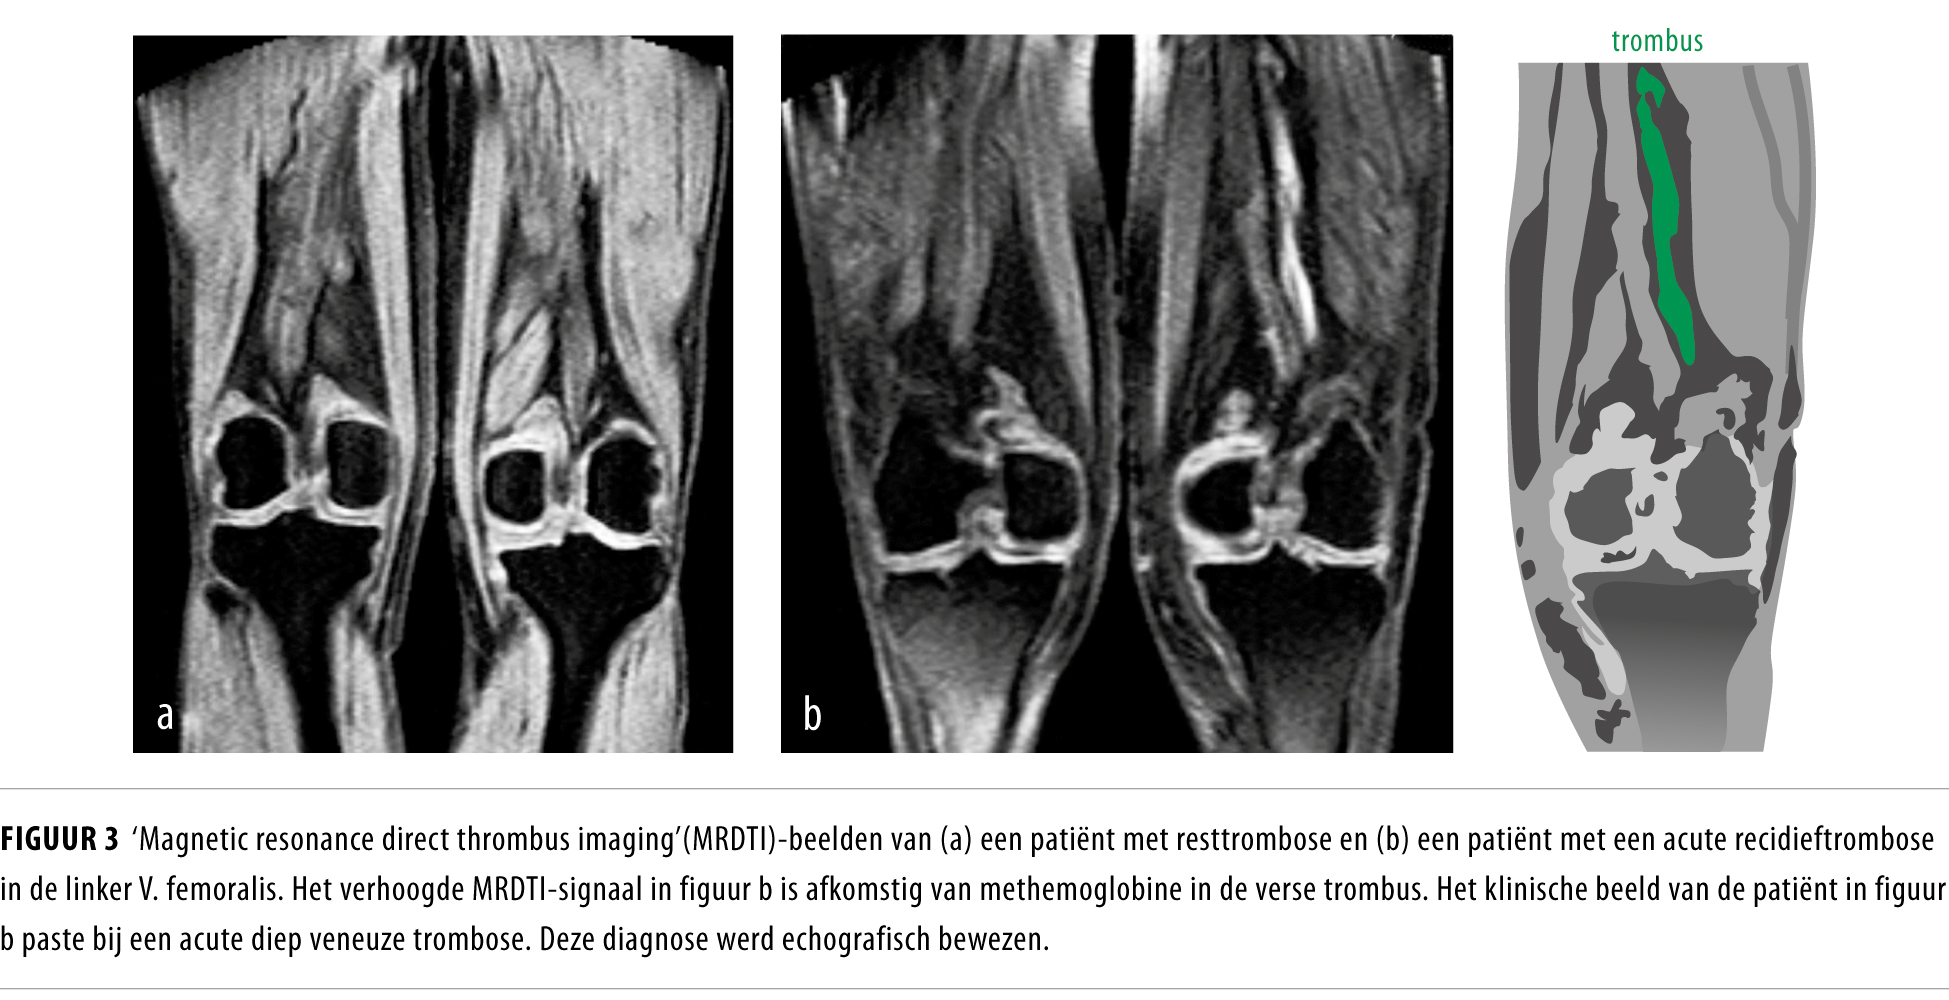

Beeldvormende Technieken Bij Diagnostiek Van Diepe Veneuze Trombose En Longembolie Nederlands Tijdschrift Voor Geneeskunde